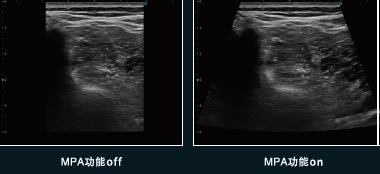

- C)自適應圖像優化技術MPA。